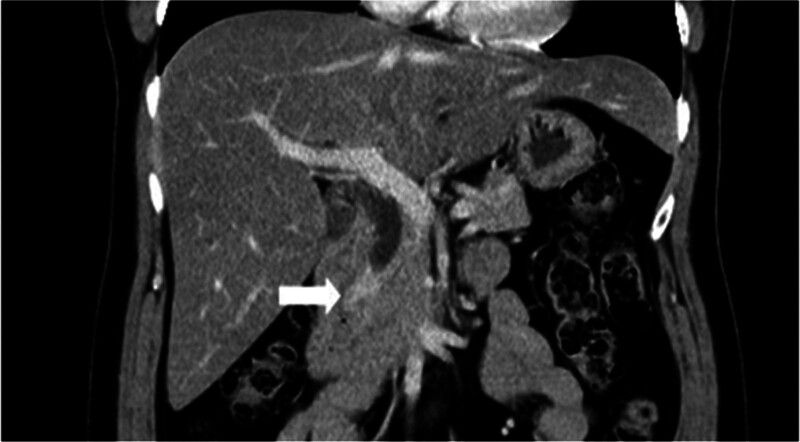

A 54-year-old woman with a medical history of hypertension and hyperlipidemia presented to the outpatient department complaining of persistent epigastric dull pain. Abdominal ultrasonography revealed significant dilation of the CBD (up to 15.2 mm); however, no obvious intraductal mass, bile duct wall thickening, CBD stones, or pancreatic head tumors were identified (Fig. 1). Subsequent abdominal CT demonstrated a contrast-enhanced tumor-like mass measuring approximately 1.6 cm in the distal CBD, characterized by wall thickening without distinct intraductal lesions. Magnetic resonance imaging (MRI) confirmed narrowing of the distal CBD with mild upstream dilatation measuring 10.9 mm, without liver, pancreatic, or lymph node involvement (Fig. 2). Physical examination of the abdomen revealed no tenderness, and the patient denied experiencing fever, nausea, vomiting, or loss of appetite. Laboratory investigations revealed an elevated level of γ-glutamyl transferase (GGT) at 130 U/L, while regular blood tests, as well as levels of carcinoembryonic antigen (CEA), cancer antigen 153 (CA153), and CA199, were within normal ranges (Table 1). Suspecting a bile duct tumor, a Whipple procedure was performed for both diagnostic and definitive treatment purposes (Fig. 3). Histological examination of CBD sections revealed adenomyomatous hyperplasia characterized by clusters of benign biliary glands embedded within fibromuscular stroma and surrounded by lymphoplasmacytic inflammatory cells (Fig. 4). The lesion exhibited no signs of malignancy, confirming its benign nature. The patient experienced a satisfactory recovery and was discharged 19 days post-surgery.

This case presents a unique aspect in which preoperative CT imaging revealed distal CBD dilation and a contrast-enhanced tumor-like mass, a presentation typically indicative of malignancy. However, the final pathology report confirmed a benign diagnosis. This scenario contributes valuable insight into the potential for benign etiologies in cases presenting with similar radiological features, thereby enhancing diagnostic considerations in clinical practice. Preoperatively, abdominal ultrasonography revealed significant dilation of the CBD. However, no obvious findings of intraductal tumors, bile duct wall thickening, CBD stones, or pancreatic head tumors were observed. Suspecting distal bile duct obstruction, an abdominal CT scan was performed, which confirmed the presence of a distal CBD tumor. An MRI was subsequently performed for confirmation. Given the strong suspicion of malignancy based on CT and MRI findings, endoscopic ultrasonography (EUS) was not performed, and the decision was made to proceed directly with surgery. During surgery, the lesion was identified as thickening of the distal CBD wall within the pancreatic head. This anatomical location explains why preoperative abdominal ultrasonography failed to detect the lesion, revealing only dilated bile ducts. If EUS had been performed preoperatively, it might have visualized the stenotic portion of the distal CBD in the pancreatic head, but it cannot reliably distinguish whether the cause is a malignant tumor, or a choledocholithiasis.